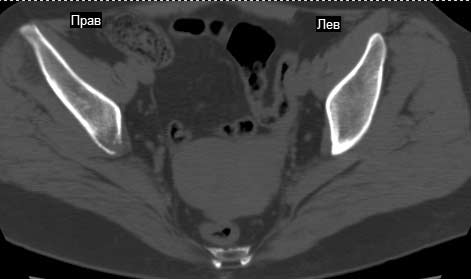

Сохранная по соматической патологии женщина ,47 лет. В 1996 г. установлен диагноз- cr левой молочной железы Т2N1Mo (2б)- проведено комплексное лечение- мастэктомия по Холстеду, ДГТ, 5 курсов ПХТ по схеме CMF. Сейчас менопауза уже 6-7 лет. В декабре 2004 года на профилактической остеосцинтиграфии с Тс99- выявлен единичный очаг повышенной фиксации препарата в зоне правой седалищной кости, рекомендована Рентгенография костей таза, выполнена- без патологии. УЗИ брюшной полости и Р-графия легких от конца апреля 2005 года - без патологии. Приблизительно 3 месяца назад появился болевой синдром в правом т/бедренном суставе с тенденцией к усилению. На рентгенограмме таза от мая 2005 года по заключению Рентгенолога очагов остеодеструкции не выявлено. Сегодня сделал ей Кт костей таза (картинки в приложении)- очаг деструкции в правой седалищной кости в зоне крыши вертлужной впадины. Что можно и нужно сделать? Жду советов, мнений, предложений по дальнейшей тактике ведения больной. С уважением, Корнев А.В.